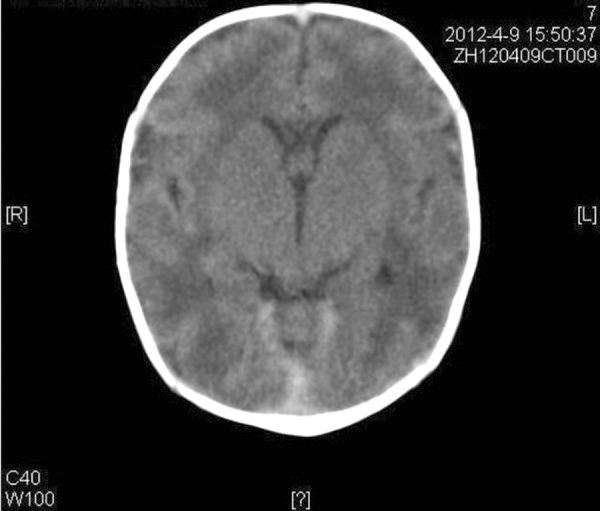

وتُعرف الحالة التي وُلدت بها الطفلة باسم انعدام الأنف الخلقي أو Arhinia، وهي من التشوهات الخلقية شديدة الندرة على مستوى العالم، حيث يولد الطفل دون أنف خارجي أو ممرات أنفية، ما يؤثر بشكل مباشر على عملية التنفس، وفقًا لما ذكرته بيانات معهد الصحة الأمريكية (NCBI).

وتحدث هذه الحالة نتيجة خلل في تكون الوجه خلال الأسابيع الأولى من الحمل، تحديدًا بين الأسبوع الثالث والثامن، وهي المرحلة المسؤولة عن تشكيل ملامح الوجه والأنف، وفي بعض الأحيان تكون مرتبطة بتشوهات أخرى في منتصف الوجه، مثل تباعد العينين أو مشكلات في الحنك والأذن.

وتُشكل هذه الحالة خطرًا على حياة المولود في أيامه الأولى، بسبب صعوبة التنفس والرضاعة، ما يستدعي تدخلًا طبيًا عاجلًا، سواء عبر توفير مجرى هوائي بديل أو إدخال الطفل إلى الرعاية المركزة.